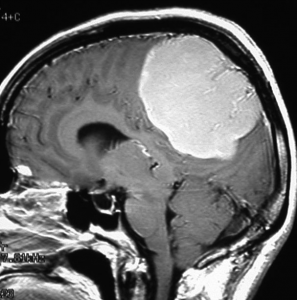

典型的な髄膜腫

この髄膜腫は中程度の大きさのものです。円蓋部髄膜種という最も多い最も手術の簡単なタイプです。麻痺や失語症やてんかんなどの症状はありません。とても美しくて若い女性の髄膜腫でしたが,子供に遺伝はしませんし,癌などと違ってタバコなどこれといった原因がなくて発生するものです。

MRIでの髄膜腫の見え方は撮影の仕方によっていろいろです。左からT1強調画像,T2強調画像,フレア画像といいます。腫瘍の横に小さく白い領域がありますが,これは脳の腫れた部分で脳浮腫といいます。髄膜腫があると周囲に脳浮腫が生じることがあります。

最も見やすいのが,ガドリニウム造影剤を注射して撮影するものです。一般的に髄膜腫は造影剤で白く映し出されます。この腫瘍は左脳側にあります。MRIの軸面という輪切りの写真では左右が逆になりますから注意してください。脳を下から見た図になっています。MRIはいろいろな方向から腫瘍を見ることができますが,右は冠状断という正面から見た図です。よく見ると腫瘍の上と下のはじっこに線状に糸を引いたように造影される部分があります。これをテールサイン(しっぽのサイン)といいます。腫瘍が硬膜に沿って延びている可能性があることを示しています。